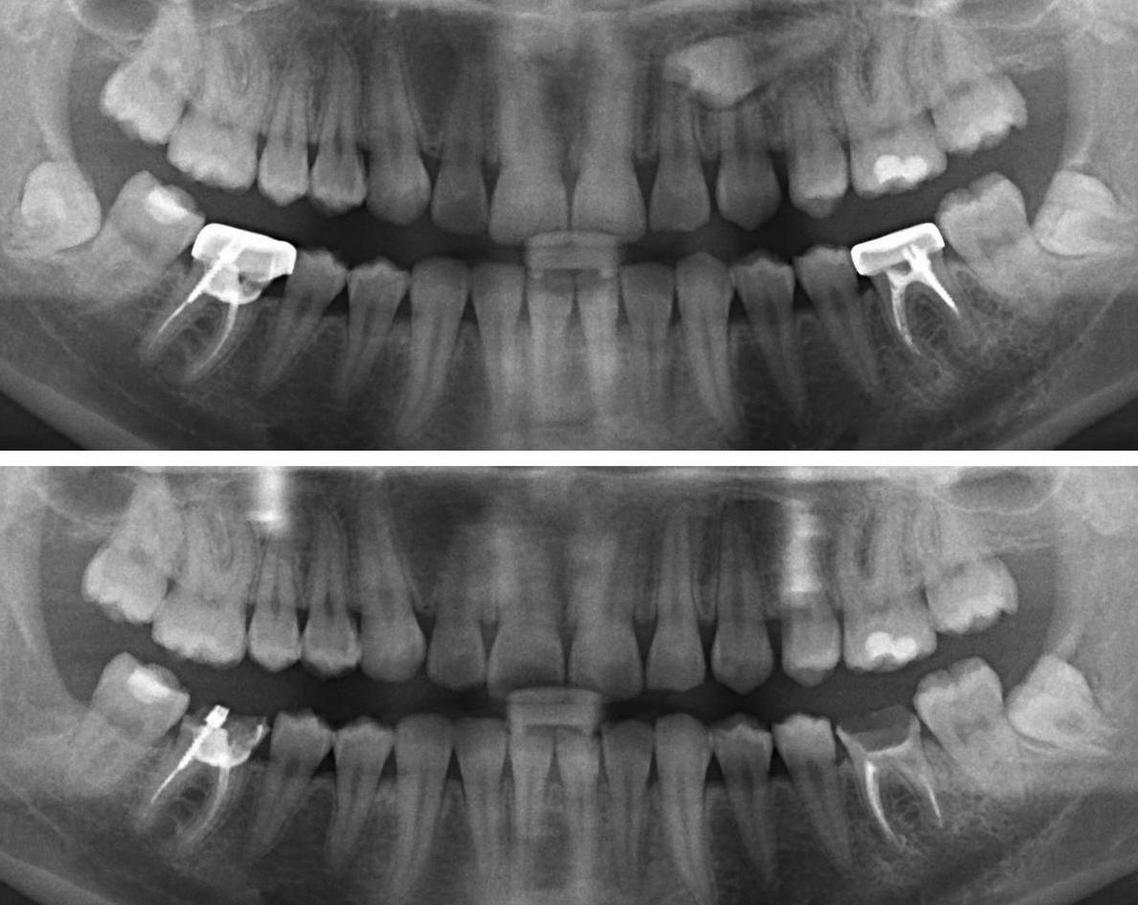

Дентальная галерея: ретинированный зуб клык и его лечение

Раздел: Компас решений